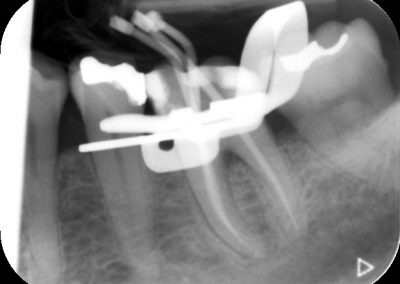

An access cavity is placed on the surface where the patient bites, to reach the root canals of the tooth. Once all the canals are identified, small files are used to remove the infected pulp.

Files of different sizes are used to eliminate bacteria and infection and to shape the canals. The canals are disinfected thoroughly with irrigants and later the canals will be sealed in 3 dimensions with a special medicament called gutta-percha to prevent reinfection of the tooth and the access cavity will be sealed with a temporary filling.